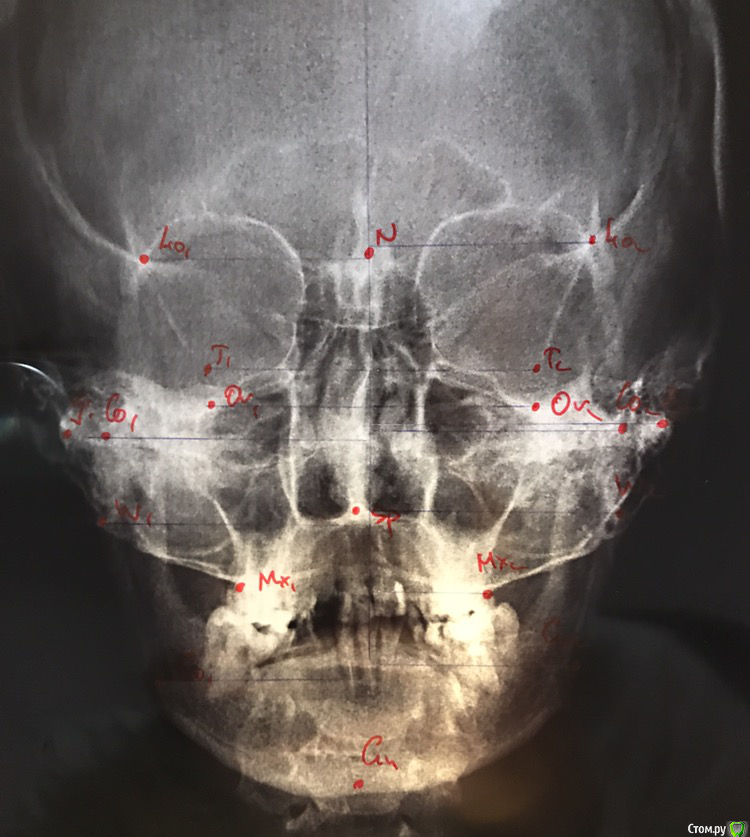

Ситуация сложная, что вполне видно на фотографиях.

верхние 1,1,2 штифты

нижние 1,1 штифты. 6-ка слева под удаление. 5-ка сверху нависает.

7-ка верх слева удалена, на ее месте стоит 8-ка (пульпит)

6-ка справа внизу удалена, 8ка справа сверху удалена.

Много депульпированных зубов, почти везде пломбы.

Имеется щелчок в суставе, но сустав не болит. Щелчки периодичные, не постоянные.